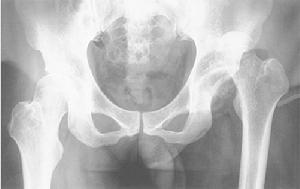

髖關節後脫位

概述髖關節由股骨頭、髖臼和韌帶等構成。由於髖臼深,股骨頭與髖臼之間有圓韌帶相連,關節周圍有堅強的關節囊、韌帶和豐厚的肌群保護,結構十分穩定。髖關節脫位(dislocation of the hip joint)多由強大的暴力引起。按股骨頭脫位後的方向可以分為前、後和中心脫位。其中以後脫位最常見。

髖關節後脫位當髖關節屈曲90°時同時在內收內鏇位,此時股骨頭已超越髖臼邊緣,不再牴觸髖臼骨面而抵在關節囊上。股骨頸前緣被髖臼前內緣擋住,形成以支點為中心的橫桿,如外力繼續作用,薄弱的後關節囊壁即發生破裂。暴力來自膝部向骨盆或骨盆推向股部即可發生後脫位。如坐在公共汽車上,髖、膝屈曲各90°並內收位(即一腿搭在另一腿上,即所謂二郎腿),骨盆固定暴力經膝部向後即可發生後脫位或者膝頂住前面靠背當猛裂剎車或撞車時暴力經軀幹骨盆推向前方也同樣可引起髖關節後脫位。若下肢內收較少,股骨頭撞擊髖臼後緣,可合併髖臼後唇撕裂骨折,或股骨頸骨折,撞擊或牽拉坐骨神經而產生神經挫傷。

類型I型 單純性後脫位不伴骨折或僅有小片骨折。

Ⅱ型 後脫位伴有髖臼後緣有大片骨折。

Ⅲ型 脫位伴有髖臼粉碎性骨折,骨折塊可大可小。

Ⅳ型 後脫位伴有髖臼緣及壁也有骨折。

Ⅴ型 脫位伴有股骨頭下骨折。

X線片可明確顯示後脫位,以及有無合併骨折。是確診的主要檢查手段。

根據患者有強大的暴力史,患肢縮短,髖關節典型表現為屈曲、內收、內鏇畸形。X線片可明確顯示後脫位,若有骨折也可看到。同時注意有無坐骨神經損傷,使膝以下感覺運動損失呈癱瘓狀態。